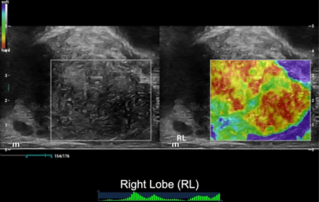

??????? ??? ?? ? ??? ??? ??? ?????, ?? ??(pelvic floor) ??? ??? ?? ??(??? ?/?? ??)? ??? ???. ? ?? ???? PVA, RVA ? PUA ?? 20┬░ ???? ?????. ? ?? ???? PVA ŌĆō 134o, RVA ŌĆō 82o ? PUA ŌĆō 119o.

??? ???? ??? ?? ????? ??? ??? ?? ?????. ????? ? ??? 30mm?? 42mm?? ??? ? ??? ??? ??? ????? ?? ? ? ?? ? ?? ? ?? ??? ??? ??? ? ????. ?? R ? ???? ?? ?? ?? ?? ?? 7mm, ?? ?? 8mm???.